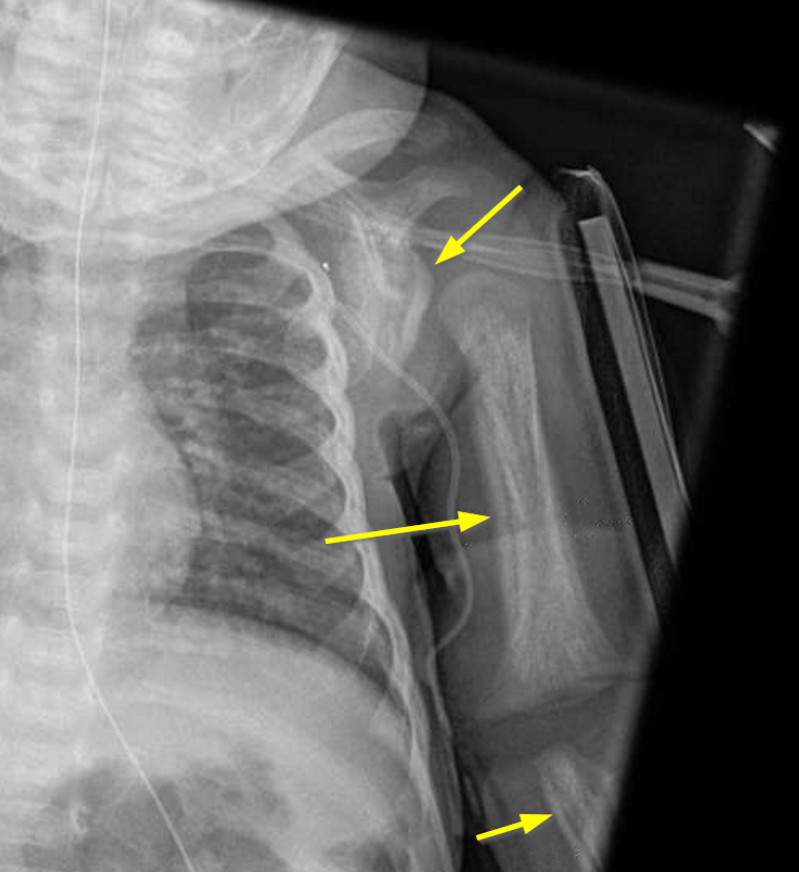

Prostaglandin periostitis Radiology Case Periosteal Injection Both botulinum toxin and dermal fillers have been widely used to address periorbital aging. To achieve consistent results utilizing facial injectables, practitioners must understand the pertinent anatomy of the forehead, temple,. Injectable anesthetic is placed adjacent to the lateral (buccal) alveolar bone. Supraperiosteal injection (commonly known as local infiltration) is indicated whenever dental procedures are confined to a localized area. Periosteal Injection.

From pubs.rsna.org